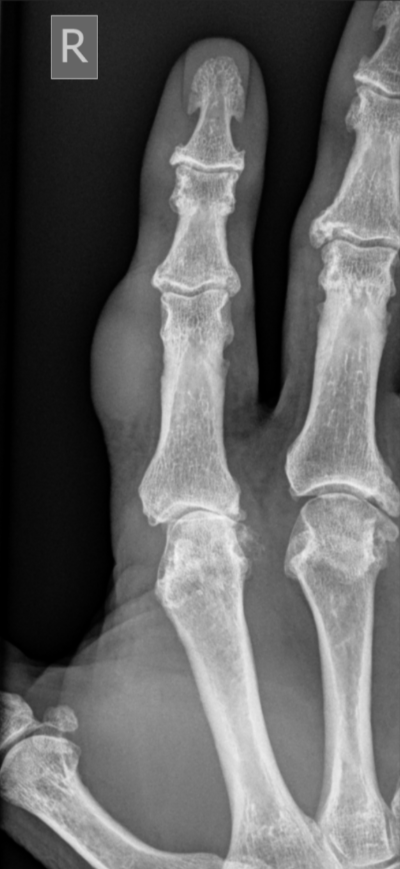

3. Giant cell tumour of tendon sheath